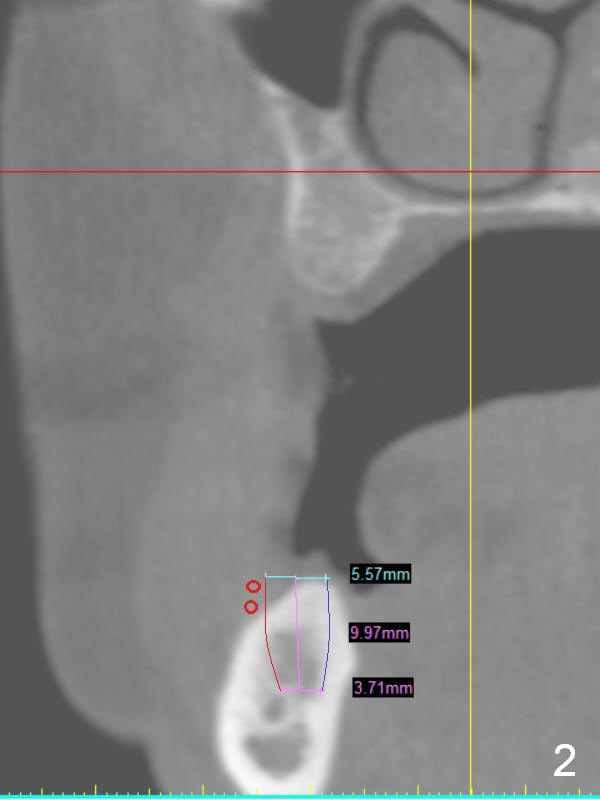

A 49-year-old lady is petit. An implant is placed at #3 and ready for restoration. The crest at #30 is narrow (Fig.1 ^). Bone density at the cortex, around the Inferior Alveolar Canal (IAC) and the medulla is D1, D2 and D3, respectively. It appears that a 10 mm bone-level implant is too close to IAC (Fig.2), whereas a 8 mm one has enough clearance (Fig.3,4). With the same diameter, there will be less thread exposure if the implant is placed a little lingually (Fig.4 (between arrows), as compared to Fig.3).